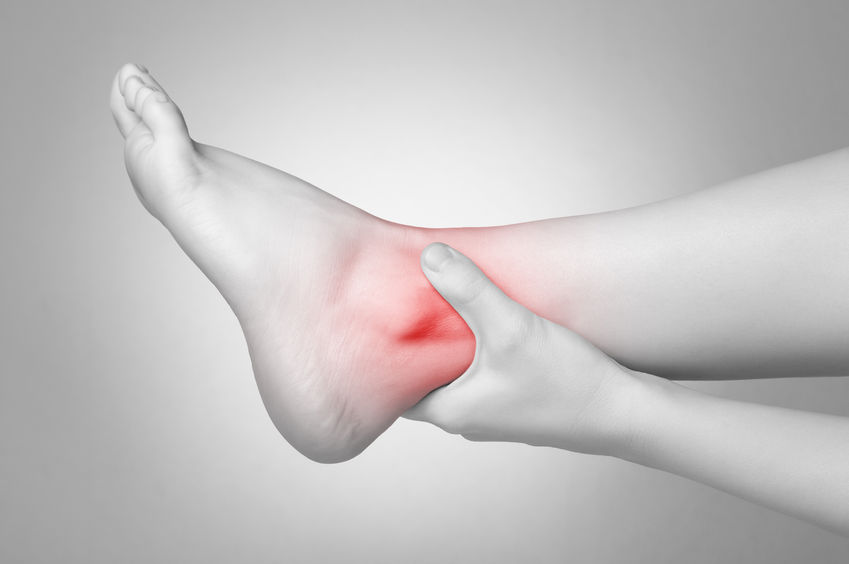

Se você sente dores persistentes, dificuldades de movimento ou já sofreu lesões que afetam sua qualidade de vida, uma consulta com um ortopedista é recomendada.

Muitos dos procedimentos são minimamente invasivos e focam no alívio da dor. Sempre priorizamos o conforto do paciente durante todo o tratamento.

A cirurgia só é indicada após esgotarmos todas as opções de tratamento clínico e minimamente invasivo.